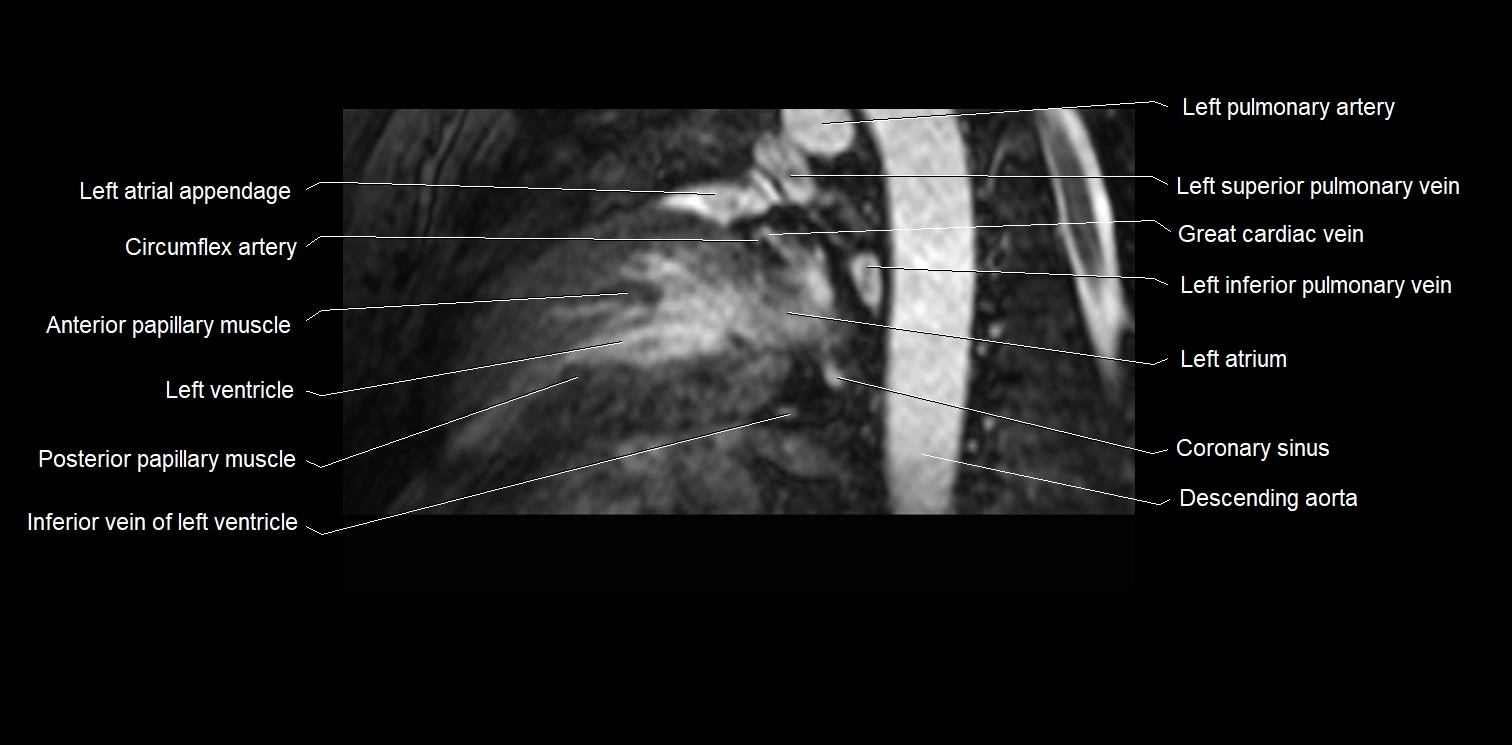

MRI image